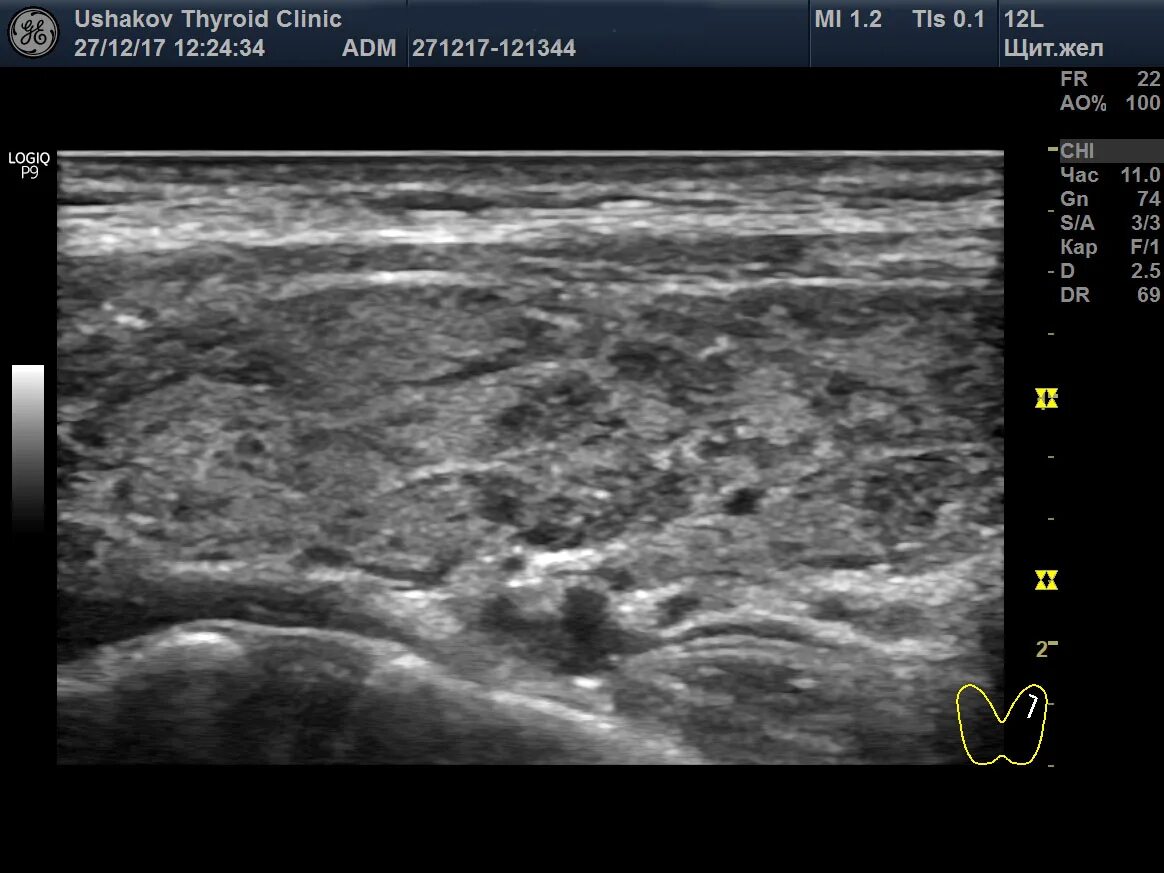

Диффузные изменения щитовидной железы на узи